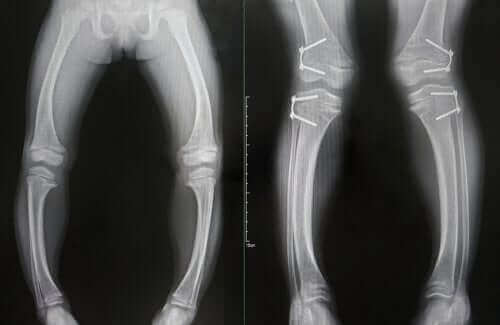

- Déformations des os, qui deviennent mous : la plus fréquente est l’apparition d’une déformation des os des jambes. Il peut également y avoir de l’usure à l’extrémité de certains os.

Le diagnostic du rachitisme est basé sur la combinaison de résultats analytiques et radiographiques altérés, ainsi que sur la présence des symptômes cliniques typiques que nous avons vus ci-dessus.